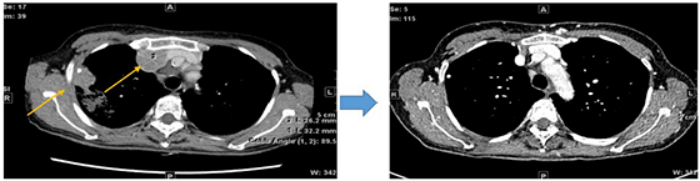

图:患者接受奥希替尼+阿来替尼联合治疗2个月前后的胸部CT扫描图

(左)一线奥希替尼治疗进展后基线胸部CT检查,显示胸膜和胸壁有转移性病变。

(右)奥希替尼+阿来替尼联合治疗2个月后胸部CT检查,显示靶病变显著缩小(-90%)。